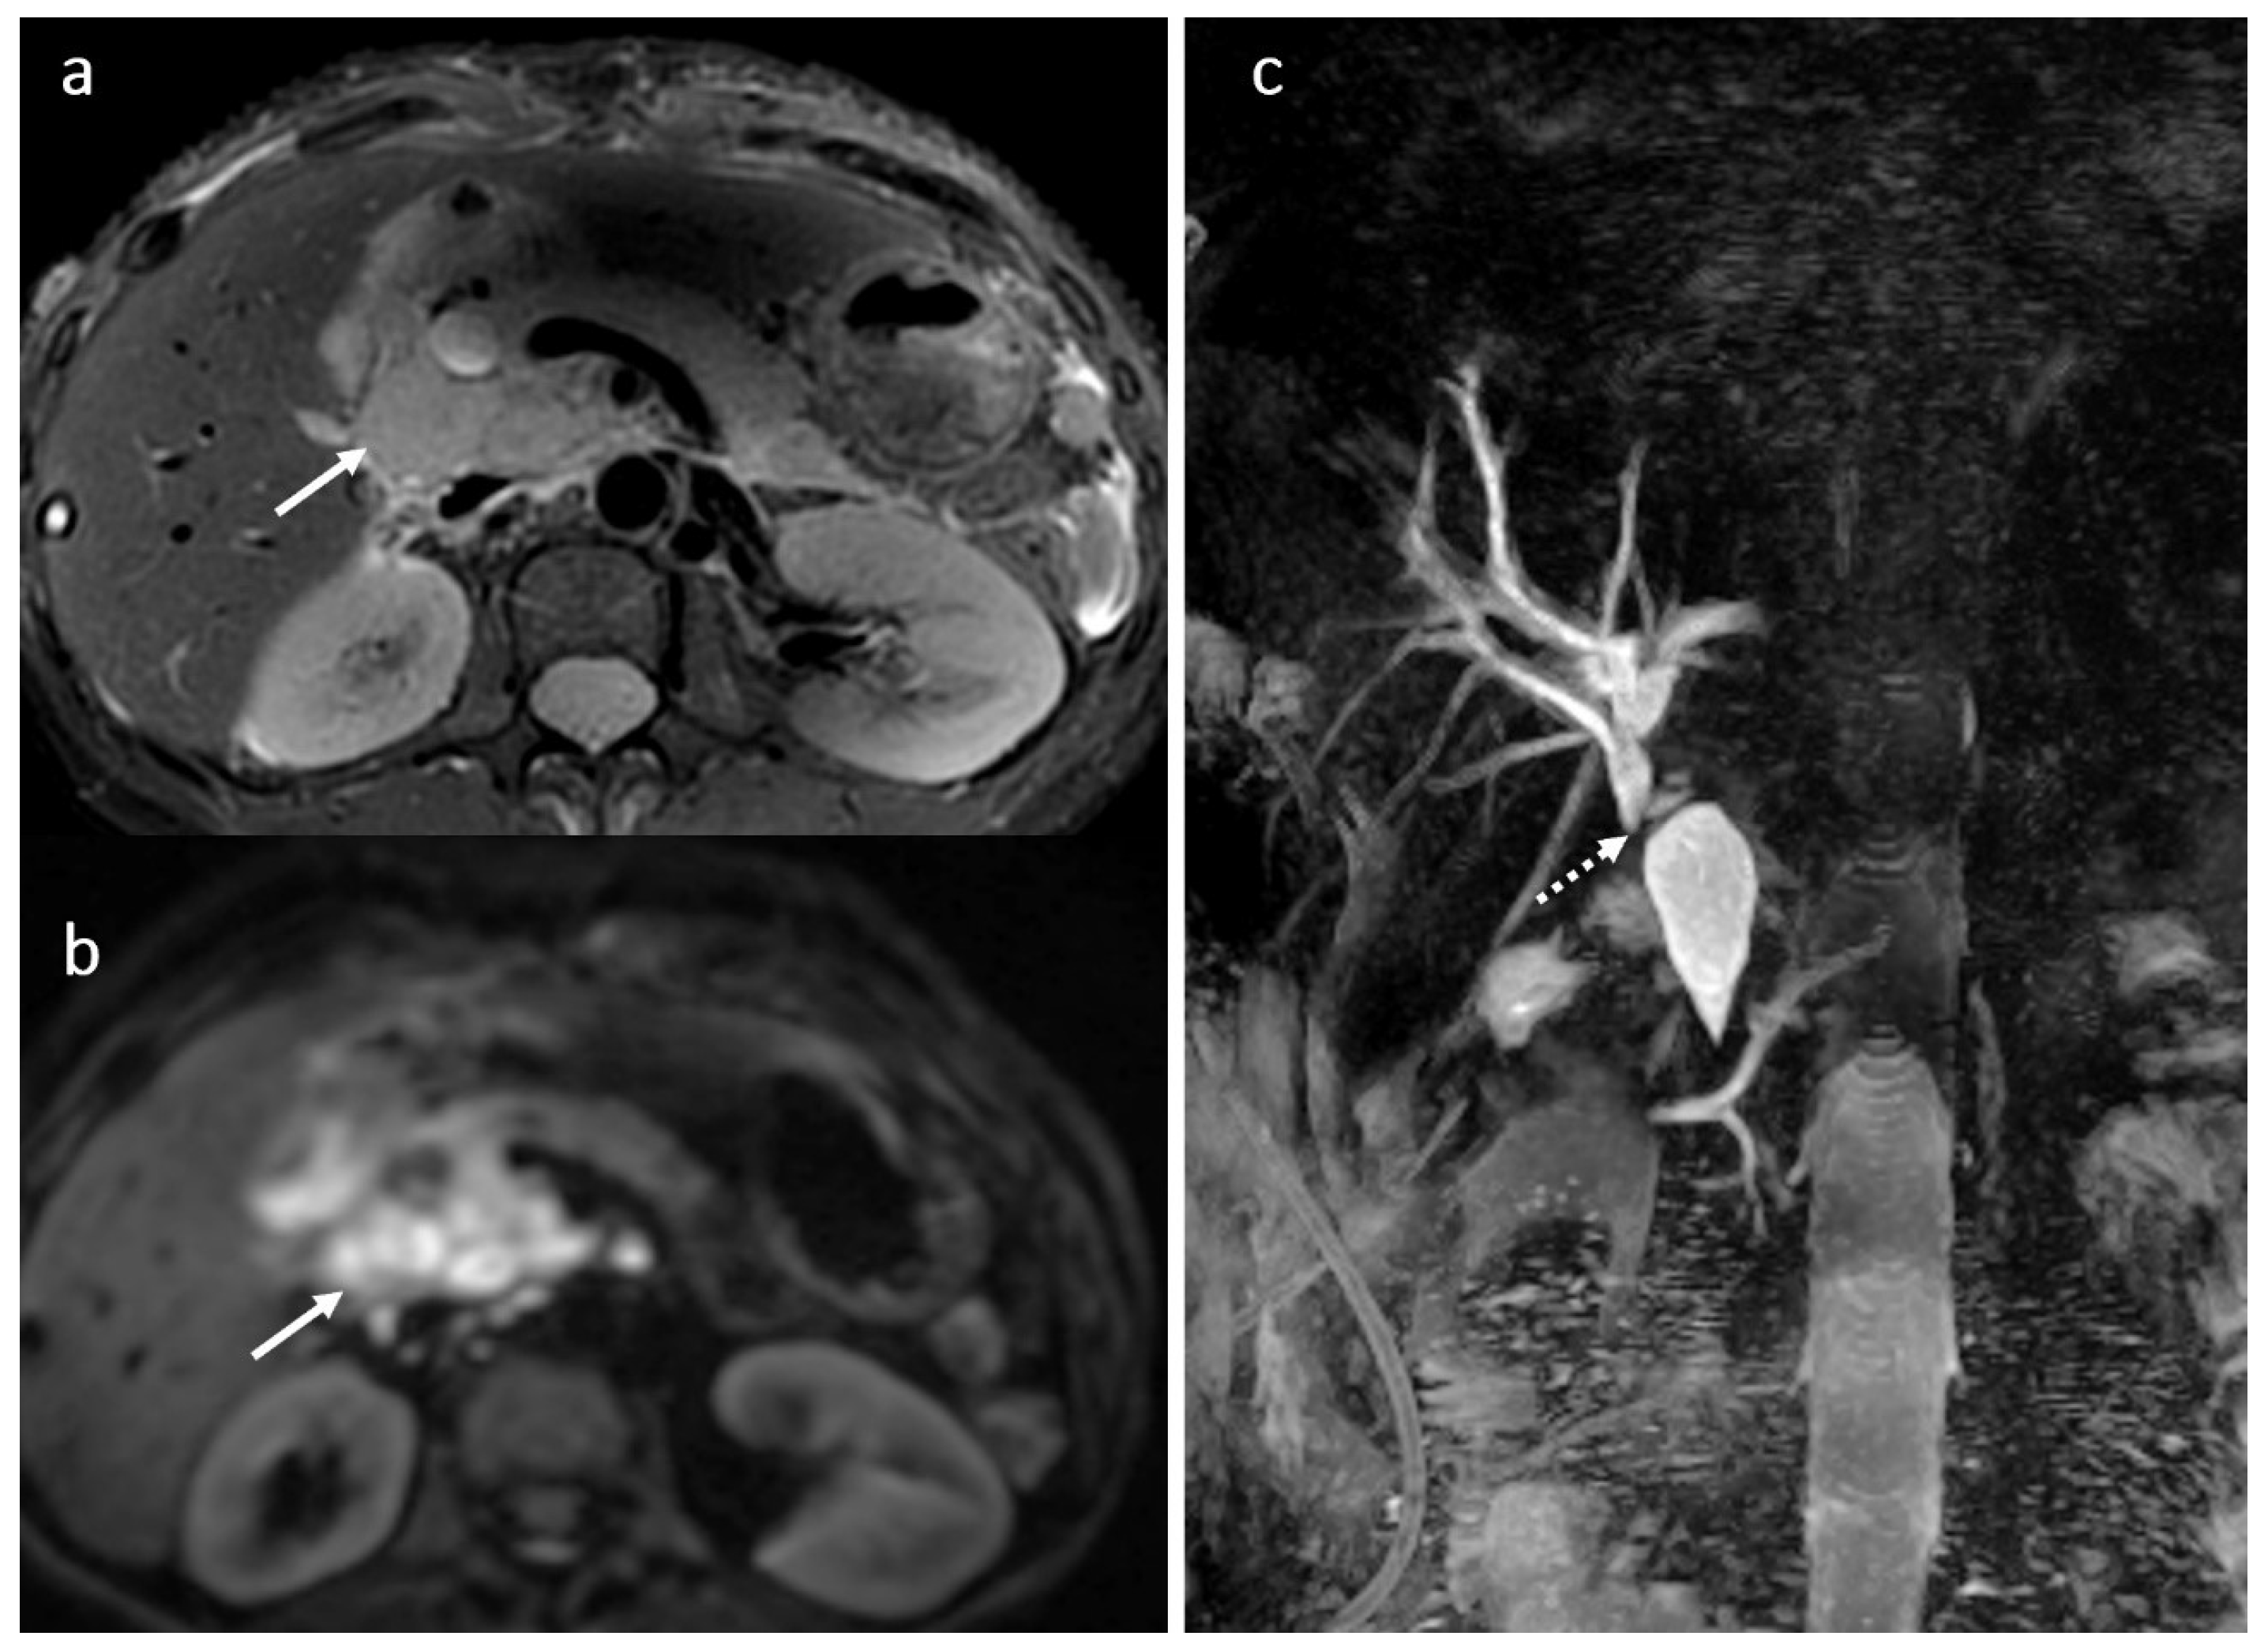

3.7. BT Lithiasis

3.8. Primary Sclerosing Cholangitis